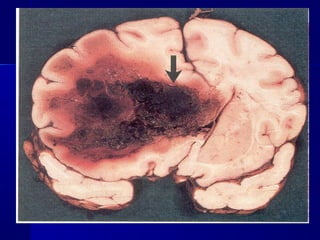

TTyyppeess ooff hheemmoorrrrhhaaggeess

 hheemmaattoommaa -- aaccccuummuullaattiioonn ooff bblloooodd iinn

ttiissssuueess wwiitthh tthheeiirr ddeessttrruuccttiioonn ((wwhhiicchh iiss

aassssoocciiaatteedd wwiitthh ttiissssuuee nneeccrroossiiss))

TTyyppeess ooff hheemmoorrrrhhaaggeess  hheemmaattoommaa -- aaccccuummuullaattiioonn ooff bblloooodd iinn ttiissssuueess wwiitthh tthheeiirr ddeessttrruuccttiioonn ((wwhhiicchh iiss aassssoocciiaatteedd wwiitthh ttiissssuuee nneeccrroossiiss))  hheemmoorrrrhhaaggiicc ssaattuurraattiioonn –– aaccccuummuullaattiioonn ooff bblloooodd iinn ttiissssuueess wwiitthhoouutt tthheeiirr ddeessttrruuccttiioonn  eecccchhyymmoosseess –– mmuullttiippllee ssmmaallll ppeetteecchhiiaass ((ppooiinntt--lliikkee hheemmoorrrrhhaaggee)) ppeerr ddiiaappeeddeessiiss  bbrruuiissee –– llaarrggee eexxttrraavvaassaattiioonnss ooff bblloooodd iinnttoo tthhee sskkiinn aanndd mmuuccoouuss mmeemmbbrraanneess